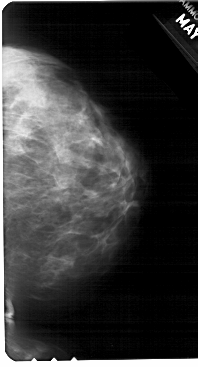

A_1685_1.LEFT_CC

LEFT_CC LINES 5491 PIXELS_PER_LINE 3136 BITS_PER_PIXEL 12 RESOLUTION 43.5 OVERLAY